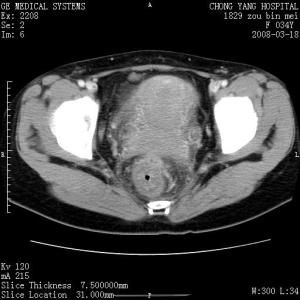

B型超聲檢查,見到子宮較大且子宮腔內有殘留胎盤或殘留胎膜影像,則可確診為胎盤殘留或胎膜殘留所致的子宮復舊不全;若見到子宮肌壁間肌瘤或子宮腺肌瘤影像,即可確診子宮復舊不全的病因。